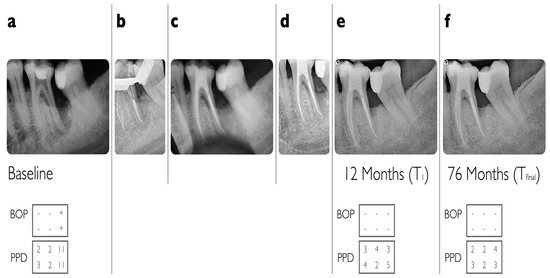

| N | T0 | T1 | Tfinal | ||

| PPD per tooth | 39 | 9.21 ± 2.15 | 5.21 ± 1.79 | NA ± | |

| PPD per tooth with final follow-up > 12 months | 23 | 9.74 ± 2.05 | 5.04 ± 1.61 | 4.87 ± 2.32 | |